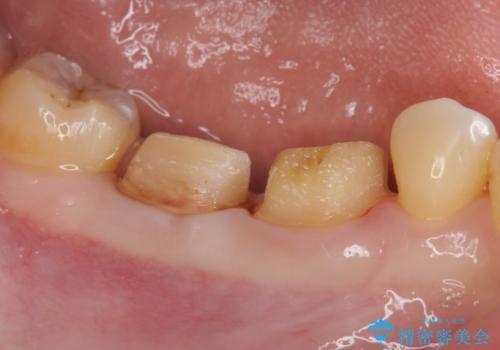

歯周ポケットの除去を併用したセラミック治療

- 歯周病や虫歯、歯の欠けなど多数の問題を他院で指摘され、今後長く持つように歯の問題をしっかりと解決したい。と希望され来院されました。

適合や審美性に優れるセラミック治療を行う前に、歯周病の問題を歯周外科を行うことで解決し将来的に不安のないような口腔内環境を整備していきます。

治療前に4-5mm程度あった歯周ポケットは全て2mm以内となり、非常に清掃性が高く、歯周病の再発しずらい環境に整えた上でのセラミック治療を実践することができました。